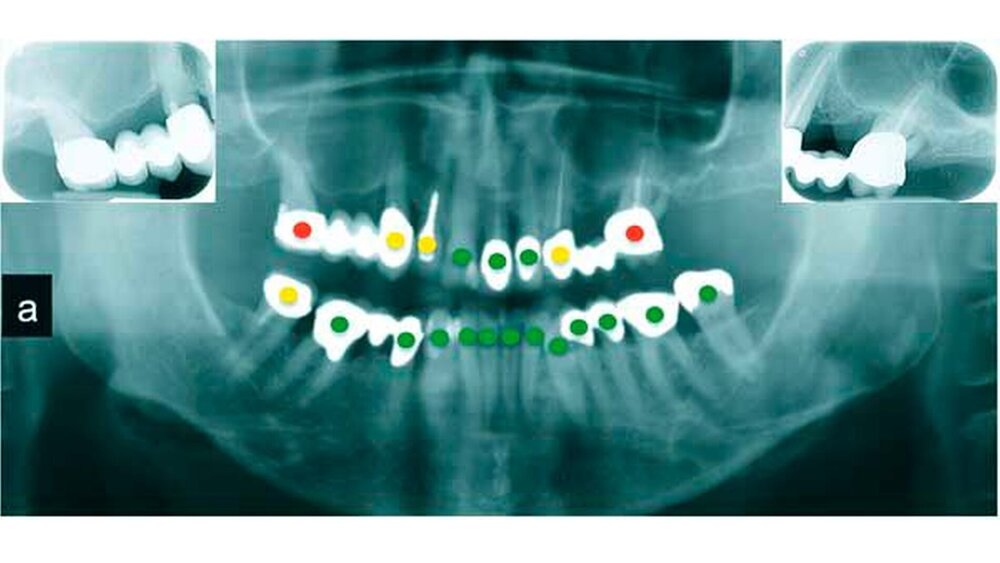

In der Erstuntersuchung ergab sich ein unauffälliger extraoraler Befund. Die Untersuchung der Lippen, der Zunge und der Mundschleimhaut zeigte keine pathologischen Veränderungen. Die dentale und parodontale Untersuchung ergab multiple insuffiziente Kronen, moderat bis teilweise stark erhöhte Sondierungswerte an mehreren Zähnen und unter anderem eine apikale Aufhellung am endodontisch insuffizient versorgten Zahn 23, der zudem noch bis auf Gingivaniveau kariös war. Der Zahn 12 war im zervikalen Bereich stark verfärbt (Rezession) und laut Röntgenanalyse mit einem Stiftaufbau versorgt. Beide Oberkiefermolaren wiesen einen hohen Attachmentverlust und einen Furkationsgrad von II-III auf. Insgesamt war der Zahnersatz ungefähr 15 Jahre alt.

Parodontal: leichte (12, 11, 22, 23, 35, 47) und moderate bis schwere lokalisierte, chronische Parodontitis an 16, 21, 36, 44, 46, 26; Furkationsgrad II-III an 16, 26

Prothetisch: prothetisch insuffizient versorgtes adultes Gebiss: insuffizienter Kronen- und Brücken-ZE an 16, 13, 23, 26, 36, 37, 44–47

Röntgenologisch: generalisierter, leichter, horizontaler Knochenabbau mit teilweise schweren vertikalen Defekten an 16, 26, 36, 44, 46; Sekundärkaries an 13,23; insuffiziente Wurzelkanalfüllungen an 23 und 47

Prognose: nicht erhaltungswürdig für die Zähne 16, 26; zweifelhaft für die Zähne 13, 23, 47